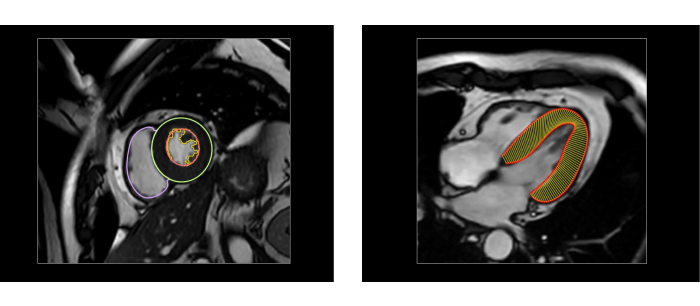

站在医生的角度,联影智能给出的答案是“全自动工作流”。方案内置独家算法,可在数秒内自动对多序列图像(心肌内外膜,水肿、延迟强化区域等)进行自动分割、特征提取、心肌运动追踪。这也意味着,在AI的加持下,医生无需像传统流程一样进行繁复地点击与操作,而是在医生打开软件之后,即可对AI基于影像自动生成的参数及分析结果进行确认或微调。而这是真正可以解放医生精力的事情。